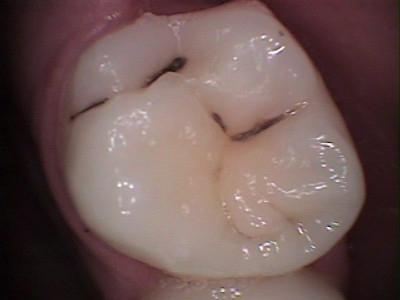

Antes

Molar superior con caries dental